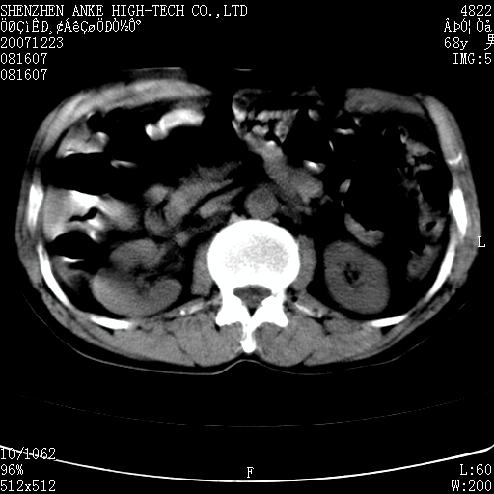

患者:男,63岁,2年前胆囊切除术后,现右上腹部剧烈疼痛近2天.

有无外伤史?右肾包膜下血肿可疑。

主要是问右肾有没有问题?患者无明显外伤史.

未见异常,病人差闭气,伪影较多.

肠管积气明显.

肠道准备不好,干扰影大。

肠道气体伪影干扰太大了,应该是干扰所致,未见明显异常。

肠道准备不好,胃底后壁显示不清,右肾改变考虑为伪影。

上腹部ct平扫未见明显异常。(肠道气体较多,患者呼吸了)

请看第一张正位片,胸主动脉象有扩张,胸主动脉瘤?